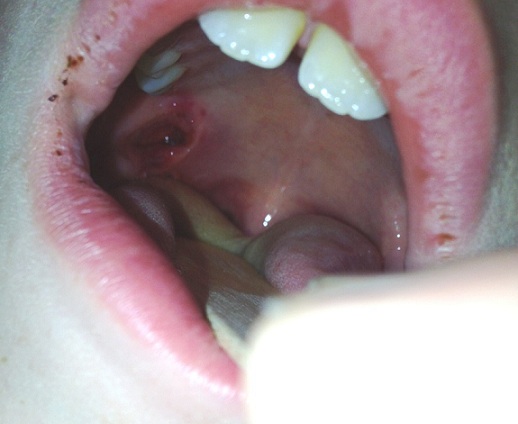

Clifton C. Lee, MD; Walker Shaw, BS; Ewa Way, MD

A 9-year-old boy presented to the emergency department (ED) approximately 30 minutes after having sustained a penetrating trauma to the posterior soft palate.